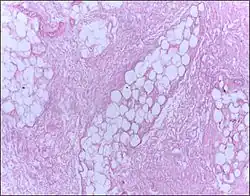

| Micrograph of breast tissue showing fat necrosis. H&E stain | |

Fat necrosis is necrosis affecting fat tissue (adipose tissue).[1] The term is well-established in medical terminology despite not denoting a specific pattern of necrosis.[2] Fat necrosis may result from various injuries to adipose tissue, including: physical trauma, enzymatic digestion of adipocytes by lipases,[3] radiation therapy,[4] hypoxia, or inflammation of subcutaneous fat (panniculitis).

The gross appearance of fat necrosis is as an irregular, chalky white area within otherwise normal adipose tissue.[1]